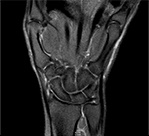

Пример МРТ лучезапястного сустава.

МР-томография кисти

Конфигурация костей запястья правильная. Угол лучезапястного сустава в пределах нормы. Форма, взаиморасположение костей запястья нормальные.

Лучезапястный и пястнозапястный суставы без особенностей. Суставные поверхности гладкие и конгруэнтные. Остеофиты и субхондральные изменения не выявлены. МР-сигнал от трехгранной, крючковатой и, более выраженно, основания 4 пястной костей (в латеральных отделах) незначительно повышен на Т2-взвешенных изображениях за счет постконтузионной отечности костного мозга.

В полулунной кости и в основании 3 пястной кости определяются мелкие костные островки диаметром до 5 мм. В остальных отделах МР-сигнал от костного мозга однородный, толщина кортикального слоя не изменена.

Локтевой диск имеет нормальную толщину, конфигурацию и структуру. Межкостные связки также без особенностей.

Запястный туннель имеет нормальную ширину, расположенные в нем сухожилия нормальной ширины и положения. Срединный и локтевой нервы в пределах нормы.

Между дистальными отделами трехгранной и крючковатой костей определяется небольшой суставной выпот (до 2 мм), также отмечается небольшое увеличение количества жидкости между полулунной и головчатой костями и вокруг основания 4 пястной кости. Мягкие ткани по наружной поверхности трехгранной кости незначительно отечны.

ЗАКЛЮЧЕНИЕ по снимку МРТ лучезапястного сустава: МР-картина незначительно выраженной постконтузионной отечности костного мозга трехгранной и крючковатой костей, а также основания 4 пястной кости с умеренным суставным выпотом. МР-признаков перелома костей запястья при настоящем исследовании не выявлено.